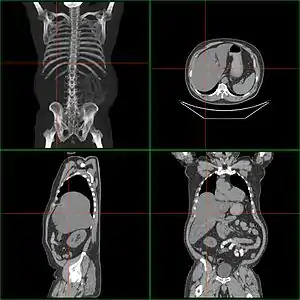

| Computerized tomography of affected person with hepatomegaly | |

Computerized tomography (CT) can help to obtain accurate anatomical information, in individuals with hepatomegaly for the purpose of a complete diagnosis.[21]